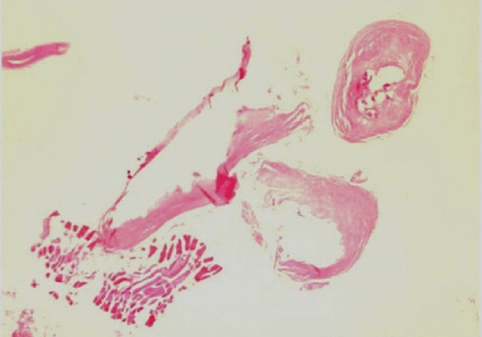

During the surgery, a small longitudinal incision was made on the upper portion of the elongated mass. A white-shiny, synovium-like piece of tissue popped out through the incision, and this was determined to be a sparganum that measured 18 cm in length and 0.5 cm in width, wriggling after removal from the patient. It was diminished to 13 cm in length and 12 mm in width after fixation in 10% formalin (Fig. 3). The calcified foci near the calf were also removed, and the pathologic examination revealed tubular tracts in the subcutaneous tissue (Fig. 4). These tracts possibly represented the pathway along which the larvae had passed. The tracks showed multiple, benign fibrocalcific nodular lesions with a few skeletal muscle fascicles, and the lesions were markedly degenerated (Fig. 5). The patient was a farmer, and she denied ingesting snake or frog meat, but she admitted drinking untreated mineral water from a local mountain. On the third postoperative day, the patient was discharged and followed up uneventfully.